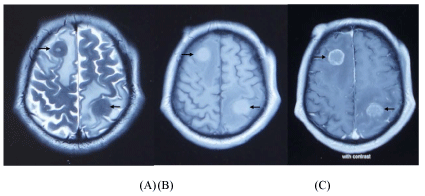

Neurogenic Pulmonary Edema: (TIA complicated with Acute Pulmonary Edema)

Getaw Worku Hassen1*, MD, PhD, Dennis Brown2, MD,Golnar Pashmforoosh1, MD, Frosso Adamakos1, MD, Tracy Barry1, DO, Rajnish Jaiswal1, MD, Leidy Gonzalez1, MD, Roger Chirurgi1 and Hossein Kalantari1

Neurogenic pulmonary edema (NPE) is a rare clinical entity that is seen in the setting of epileptic seizure, head injury and cerebral hemorrhage. NPE in the setting of transient ischemic attack (TIA) has not been reported before.